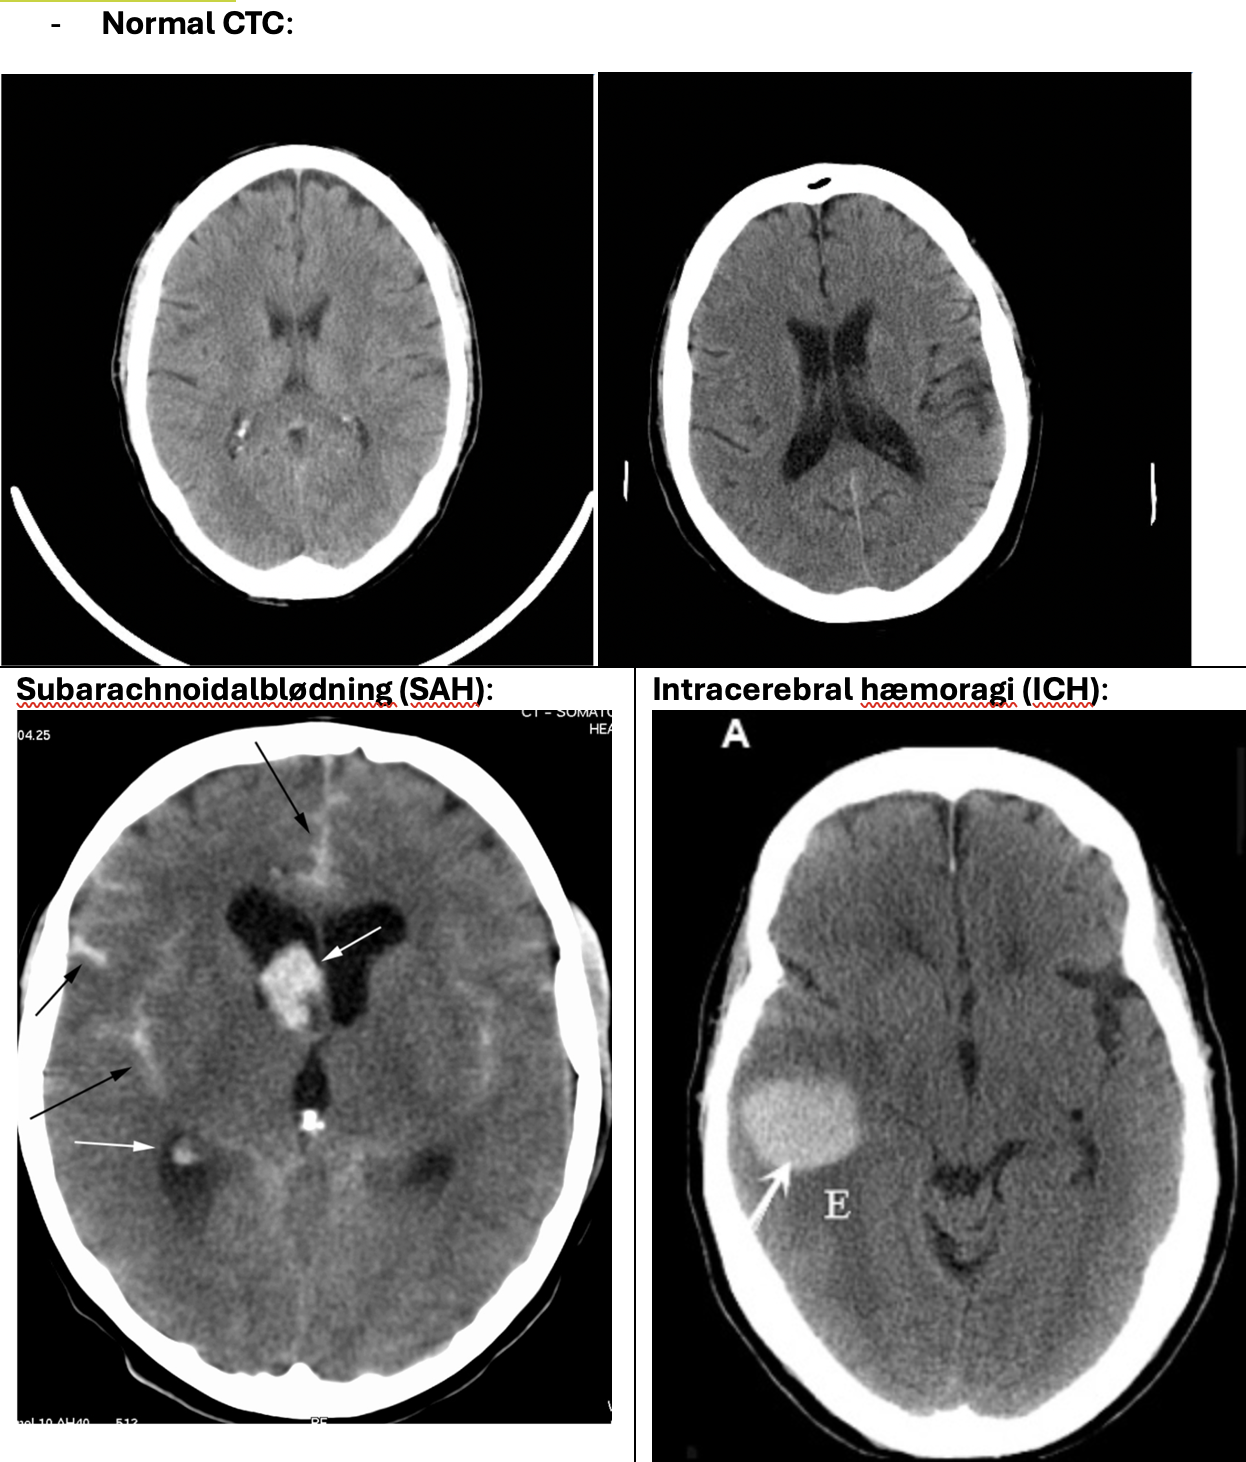

Hjerneblødning:

Subarachnoidalblødning (SAH)

Intracerebral hæmoragi (ICH)